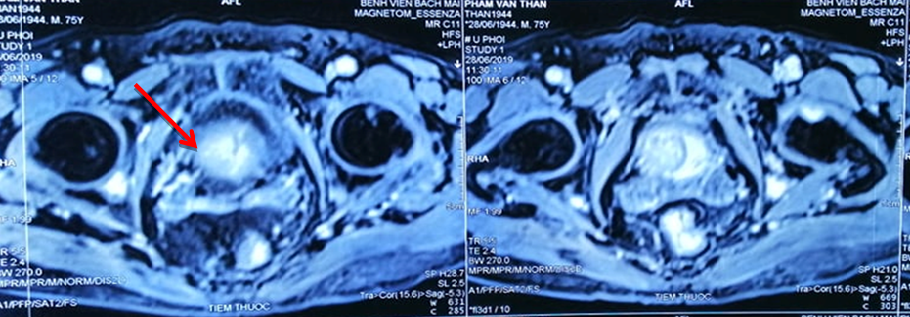

Đơn cử như trường hợp bệnh nhân Phạm Văn Thân, 76 tuổi mắc cùng lúc ung thư phổi di căn não, xương và ung thư tuyến tiền liệt giai đoạn muộn.

Do 2 ung thư đều ở giai đoạn muộn, bệnh nhân có rất nhiều hạch ở trung thất, hạch thượng đòn, tổn thương xương đa ổ. Khối u ở phổi đã to 6x4 cm, 3 khối u não kích cỡ 0,5-0,7 cm, u tuyến tiền liệt to gần 3 cm.

Dù bệnh nhân tuổi cao nhưng sau 3 tháng, kết quả điều trị rất tốt, bệnh nhân đỡ khó thở, đỡ đau đầu. Sau 9 tháng, ông Thân hết khó thở, không ho, không đau tức ngực, tăng 3kg, hết tiểu khó, khối u ở phổi xơ hoá, khối u trên não biến mất, khối u tuyến tiền liệt giảm còn 2 cm.